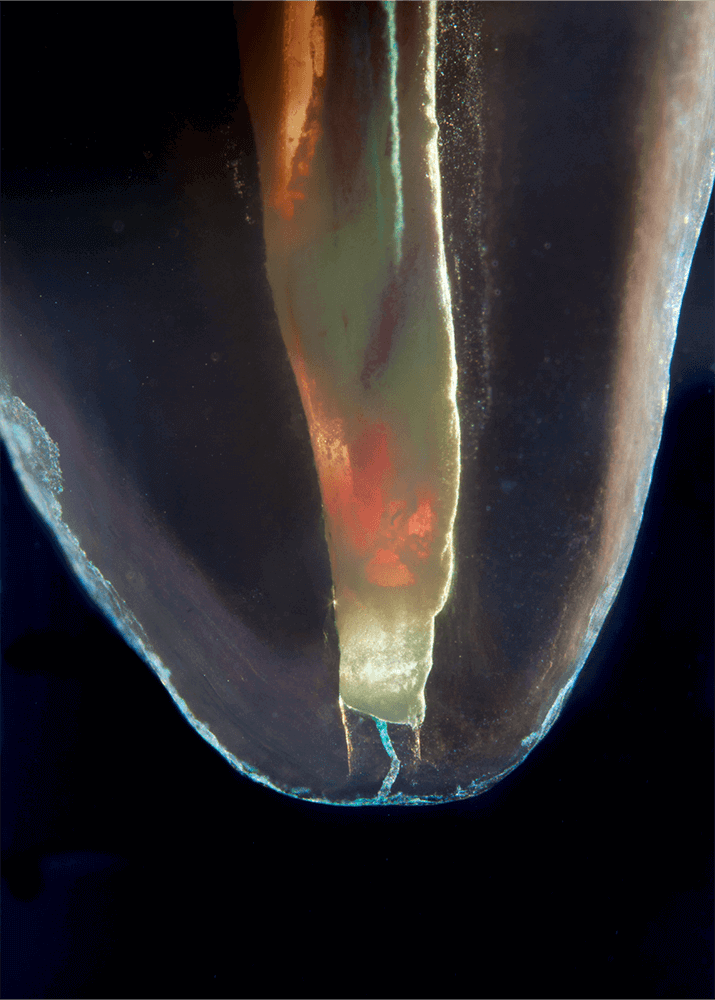

Das Verfahren, Zähne in durchsichtige Präparate zu überführen ist schon über 100 Jahre alt. Aber erst durch die Weiterentwicklung der alten Technik und die Kombination mit moderner Fotografie sowie der Entwicklung eines geeigneten Gefäßes zur Fotografie ist es meinem Vater Dr. Holm Reuver gelungen, einzigartige Bilder vom Inneren der Zähne aufzunehmen.

Die Bilder sind in verschiedenen Größen wählbar und auch als POPART-Variante erhältlich. Sie sind hervorragend geeignet für die Beratung von Patienten vor endodontischen Behandlungen, aber auch ein beliebter Eyecatcher im Wartezimmer. Außerdem haben die Bilder einen bedeutenden Stellenwert für die Erforschung der Pulpatopografie und für die Lehre im Bereich der Endodontie.